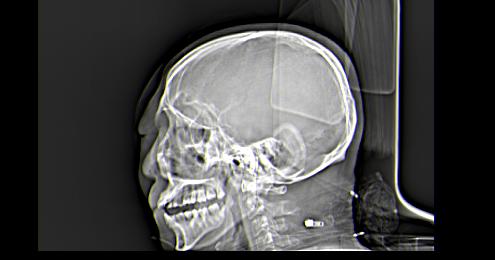

以下是引用皎皎白驹在2006-11-29 8:48:00的发言:[br]影像表现:双侧筛窦和上颌窦、鼻腔内均密度增高,右侧视神经增粗、弯曲,左筛窦顶部筛板及右侧纸板近视神经孔区可见骨折线。[br]结合临床表现考虑:右侧筛窦纸板近视神经孔区骨折致右侧视神经损伤。最好做个眼眶冠状扫描,更明确右侧视神经管是否狭窄。

以下是引用w_jianhua在2006-11-29 10:07:00的发言:[br]影像表现:双侧筛窦和上颌窦、鼻腔内均密度增高,右侧视神经增粗、弯曲,左筛窦顶部筛板及右侧纸板近视神经孔区可见骨折线。[br]结合临床表现考虑:右侧筛窦纸板近视神经孔区骨折致右侧视神经损伤。最好做个眼眶冠状扫描,更明确右侧视神经管是否狭窄。 [br] [br]支持[br]

以下是引用守望可可西里在2006-11-29 9:46:00的发言:[br][quote]以下是引用皎皎白驹在2006-11-29 8:48:00的发言:[br]影像表现:双侧筛窦和上颌窦、鼻腔内均密度增高,右侧视神经增粗、弯曲,左筛窦顶部筛板及右侧纸板近视神经孔区可见骨折线。[br]结合临床表现考虑:右侧筛窦纸板近视神经孔区骨折致右侧视神经损伤。最好做个眼眶冠状扫描,更明确右侧视神经管是否狭窄。